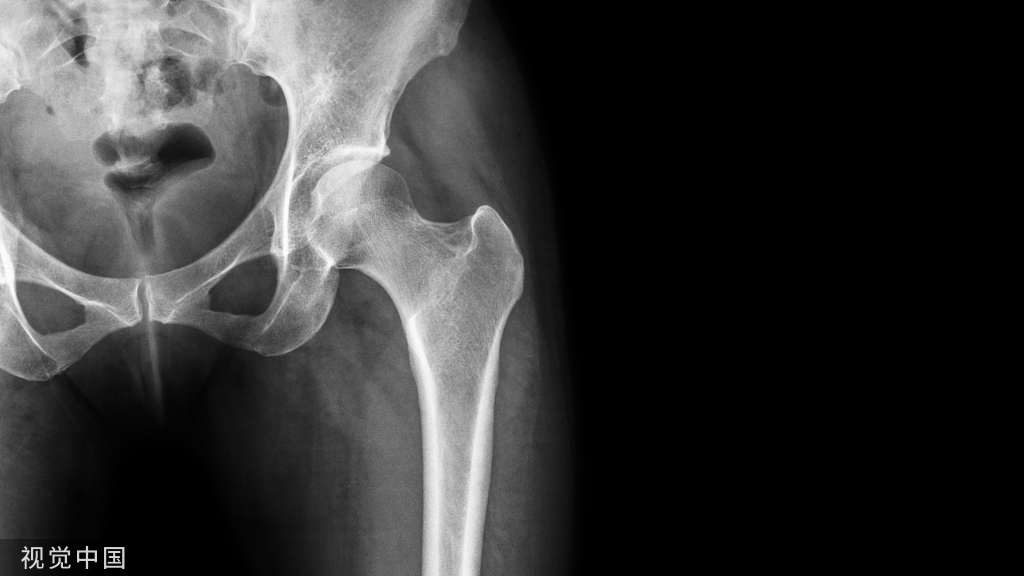

椎弓根狭窄(A)和椎动脉高跨(B)

B:椎弓根狭窄,椎动脉高跨右侧椎弓根螺钉置入风险高

B:椎弓根狭窄,右侧椎动脉高跨